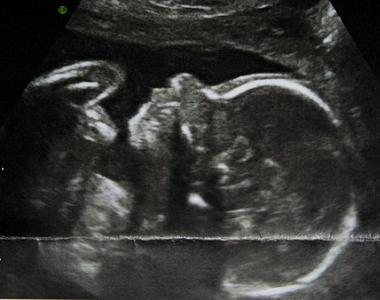

Rodíme ONLINE - dvě vyštření u lékaře, Chriskindl

Eva má za sebou dvě lékařská vyšetření. Test na těhotenskou cukrovku dopadl výborně a lepší zprávy přineslo i ultrazvukové vyšetření. Prostupování živ...

Rodíme ONLINE: miminko se otočilo

Kontrola u lékaře přinesla dobrou zprávu - miminko se otočilo. Nyní Eva řeší, kdo pohlídá Sophii, až bude rodit. Doufá, že se podaří někoho najít, aby...